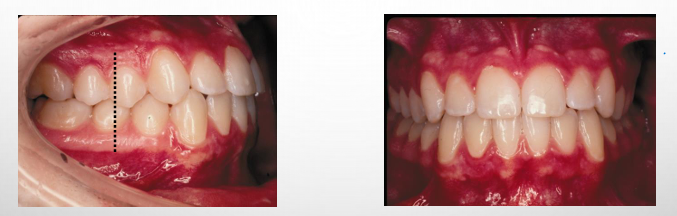

intraoral exam- sagittal

-use the buccal photos and diagnostic models

-molar/posterior segment relationship (class I/II/III)

-overjet

Angle classification

-classifications based on the relationship of the MB cusp of the maxillary first molar and the buccal groove of the mandibular first molar

-if this molar relationship exists, then the teeth can align into normal occlusion (ideal overbite and overjet in absence of other mal-occlusive anomalies)

-treat to class I

normal occlusion

-MB cusp of the maxillary first molar is aligned with the buccal groove of the mandibular first molar

-there is alignment of the teeth, normal overbite and overjet, and coincident maxillary and mandibular midlines

class I malocclusion

-a normal molar relationship exists but there is crowding, misalignment of the teeth, crossbites, etc.

class II malocclusion

-most common

-a malocclusion where the molar relationship shows the buccal groove of the mandibular first molar distally positioned when in occlusion with the mesiobuccal cusp of the maxillary first molar